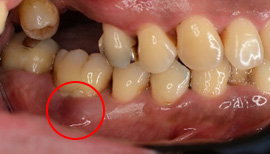

治療前

赤丸の部位が根分岐部病変が3度です。根の間が骨がなく、黒く透過像になっています。